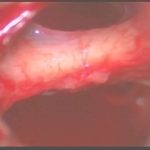

術中写真

摘出 前

摘出 中

摘出 後